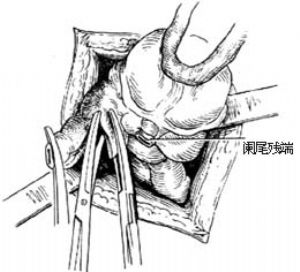

12.9 9.闌尾殘端處理

用3把尖端夾有小棉球的直止血鉗將棉球分別蘸上純石炭酸(或5%碘酊)、75%酒精和生理鹽水,依次在闌尾殘端粘膜面塗擦,然後棄去保護盲腸的鹽水紗布[圖1 ⑻]。

圖1 ⑻殘端消毒處理

12.10 10.包埋闌尾殘端

助手用左手持無齒鑷提起荷包縫線線頭對側的盲腸壁,右手持夾住線結的止血鉗,將闌尾殘端推進盲腸腔內,同時術者上提並收緊荷包縫線,使殘端埋入荷包口,結紮後剪斷線頭[圖1 ⑼]。

圖1 ⑼包埋殘端

圖1 ⑼包埋殘端

有人主張不包埋殘株,僅用絲線結紮闌尾根部即可,用此法時最好用縫針稍縫一點闌尾漿膜再結紮闌尾以免滑脫,此針縫合勿穿過闌尾腔。在闌尾周圍盲腸壁明顯水腫質脆時,不宜勉強做荷包埋沒殘株,只做單純結紮更爲安全。如擬用周圍組織覆蓋闌尾殘端,可用闌尾系膜殘緣或附近腸脂垂,切勿牽拉大網膜與殘端固定。